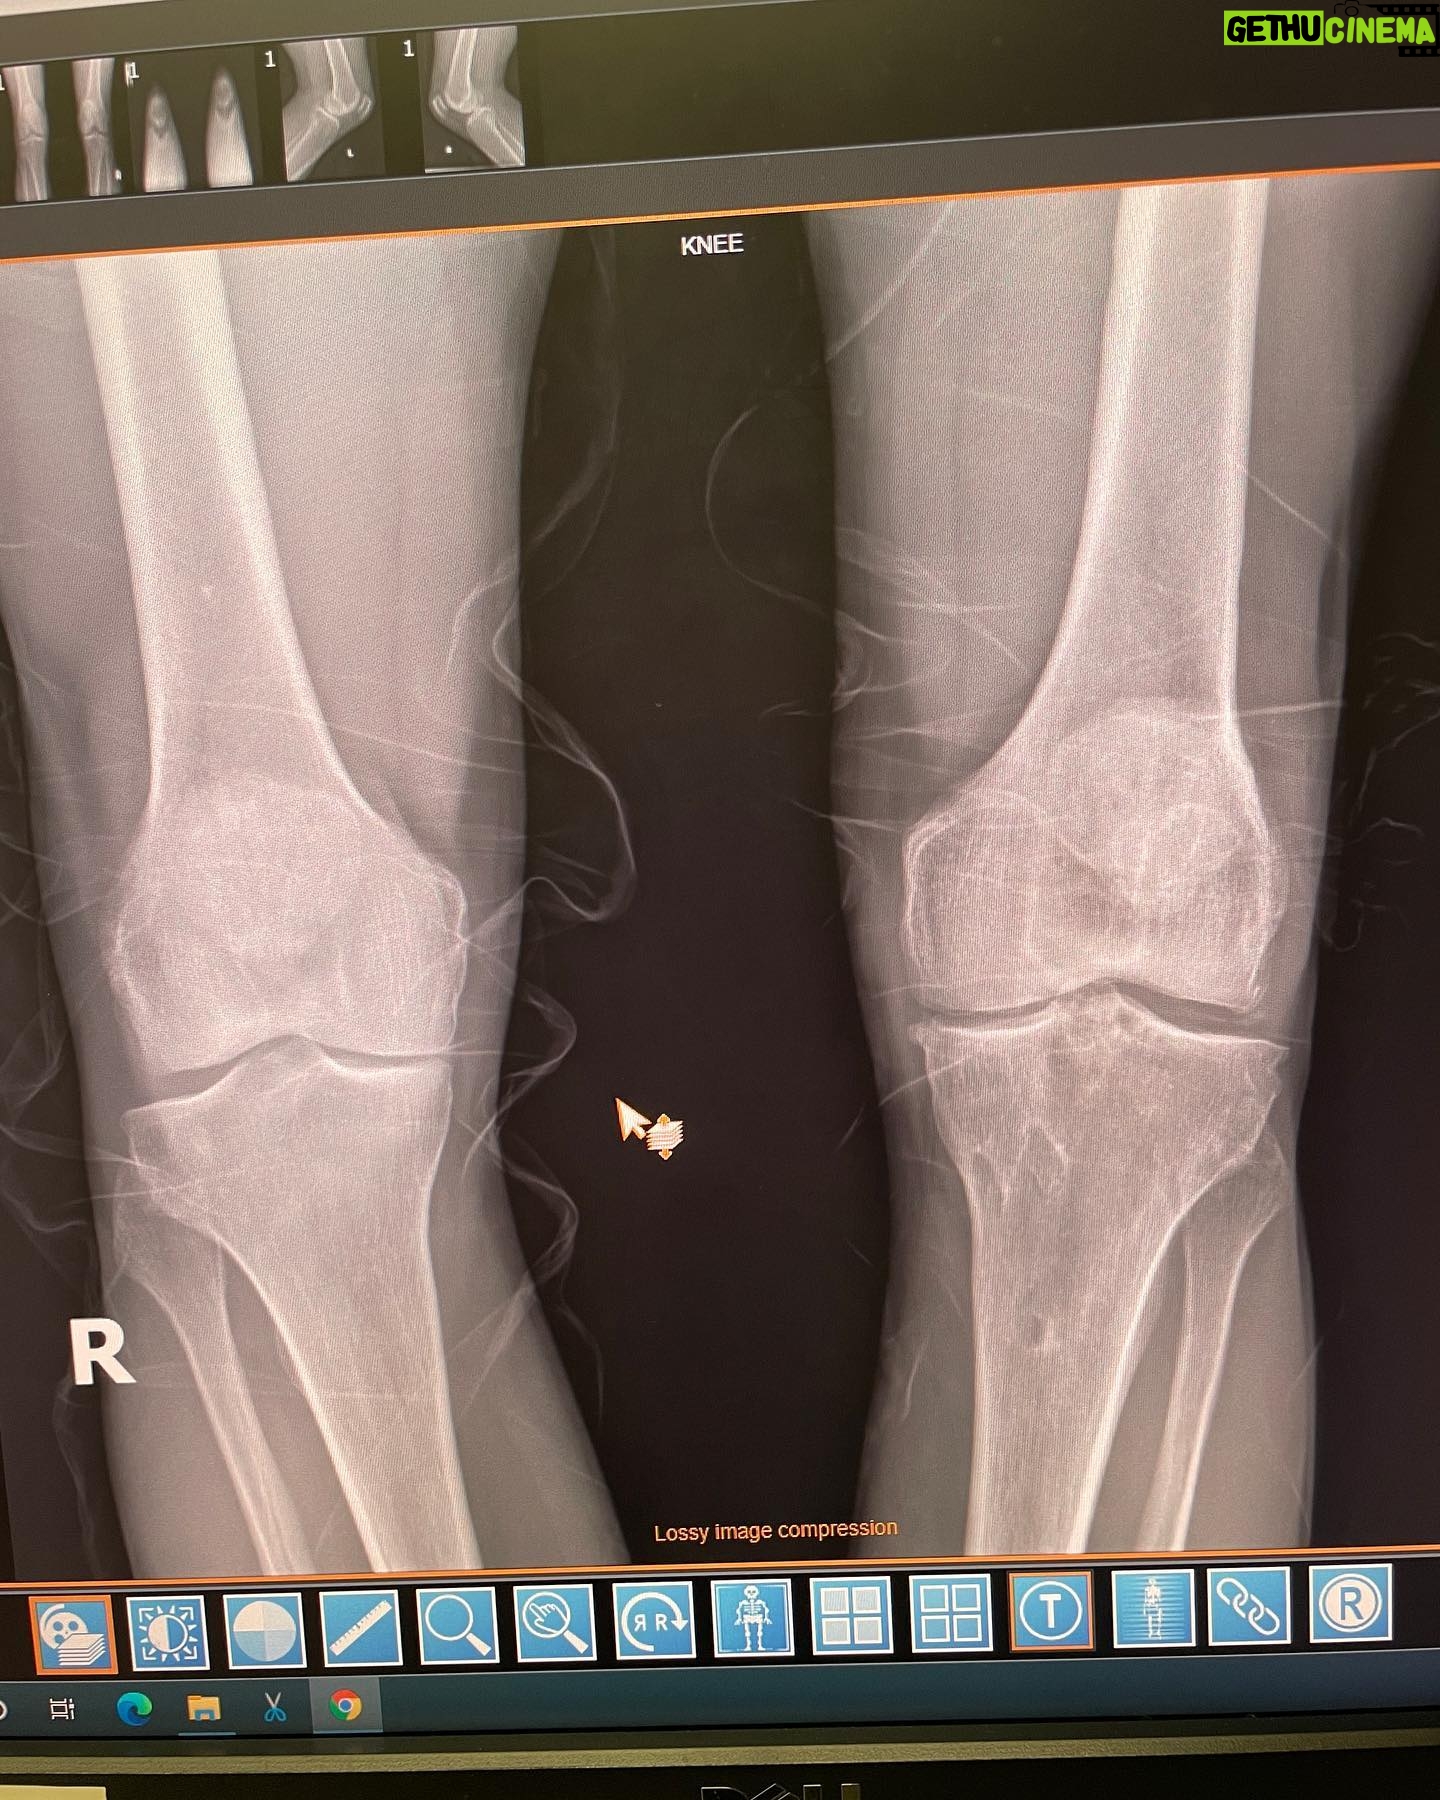

Caption : Seeing is believing, I’m always searching for the latest innovations with orthopedic medical science and was connected with @bioxcellerator_ through a good friend of mine @wolfmate about 2 years ago. I have had countless joint injuries and surgeries over the last 40 years and have some significant degeneration in several joints but the weight bearing joints are the most chronically painful. I have had 4 knee reconstructions on my left knee and about to have the 5th. Both of my knees have cartilage degeneration / arthritic changes from years of heavy abuse. BioXcellerator treated both knees along with every other joint in my body 14 months ago. Just prior to these treatments I had MRI scans and X-rays on every joint in my body. Here is proof of what the mesenchymal stem cells can do for degenerative joints. The first of these 2 films was shot 14 months by @dr.fabilus just prior to my treatment late June 2021 and the second film was shot 2 days ago September 9th 2022 by @dr.fabilus . The joint spacing has increased between my tibial plateau and my femoral condyle, which shows some level of cartilage regeneration in this 14 month time period and it will continue to improve for the next year or so! When I built this relationship with @bioxcellerator_ I told them I wanted to document the process and the results of my treatments and be completely transparent about the findings and they were so confident in the outcome they were happy for me to share the results. I’m so amazed by these results and very excited to be working with the most advanced scientists, doctors and business in the stem cell movement. Thank you so much @bioxcellerator_ @ericstoffers.ceo @dr.karolynnhalpert @dr_alejo @anahoyosf @dianis747 @drwilliamprevite @dr.fabilus @anirpo90 @joeygranathLikes : 6111

6.1K Likes – Danny Way Instagram